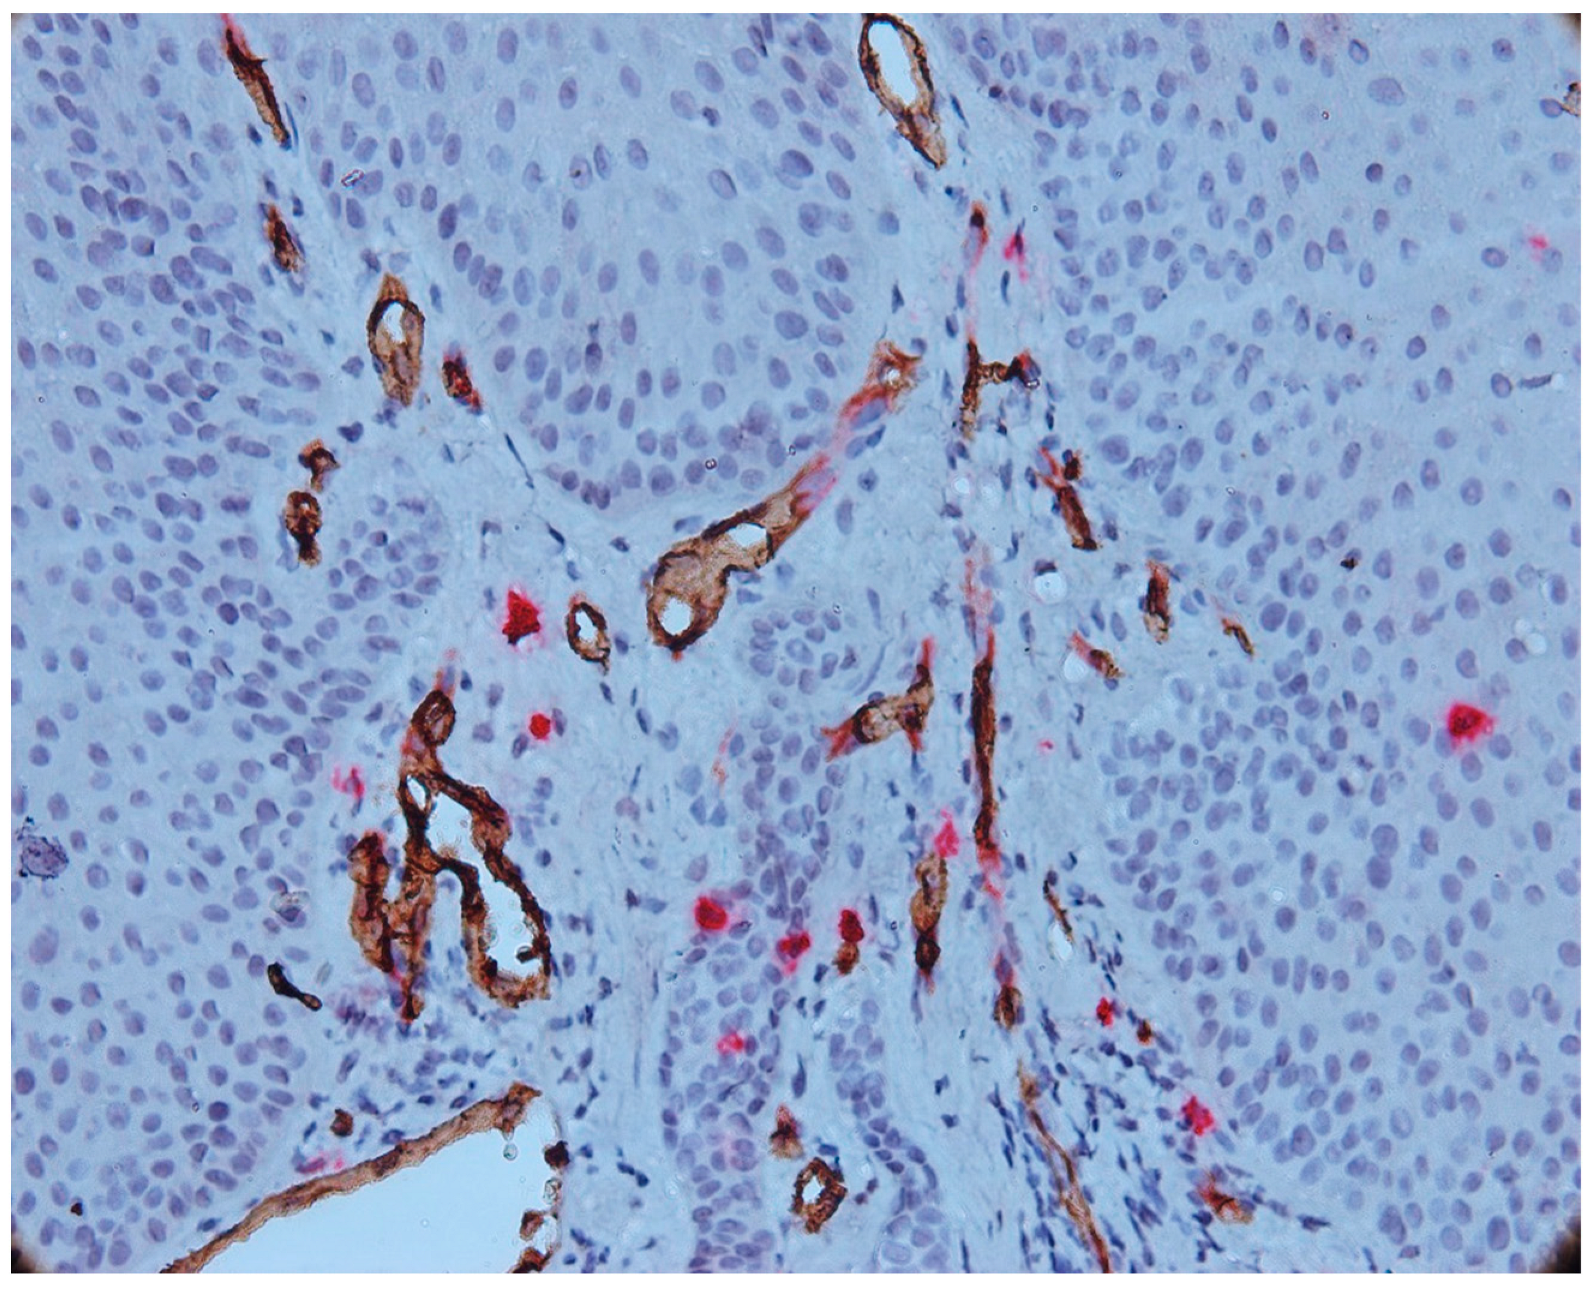

3.3. Aspects of Microvessels

3.4. MCD and MVD